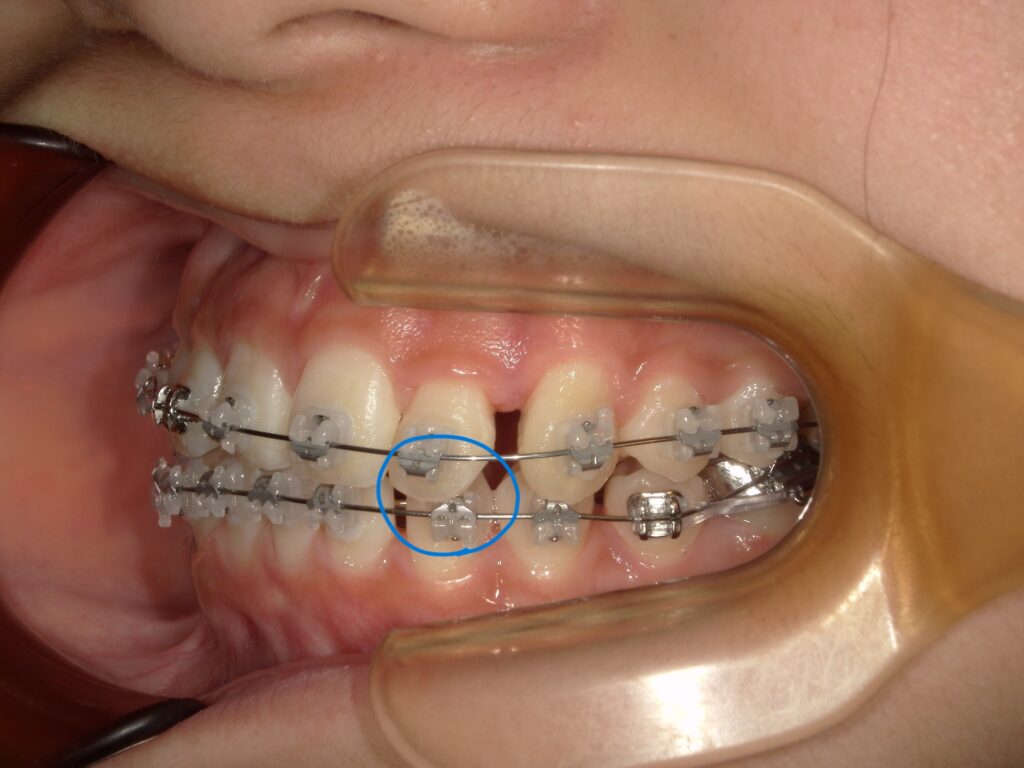

◆ ⑥ 噛み合わせが深い人

ガチっと深く噛み込む噛み合わせの人は、

上の前歯が下のブラケットに当たり、外れることが多発します。

深い噛み合わせの人は、

「治療初期ほど外れやすい」

という特徴があります。

また、過蓋咬合の場合でなくても噛み合わせ位置の関係で装置が外れやすいこともあります。

画像のようにブラケット装置と上の歯の切縁が当たることで装置が何度も外れる、という状態です。

この場合は、ブラケットを違うものに変更するか、歯が動き噛み合わせが整ってくるまで様子見していくことが多いです。・